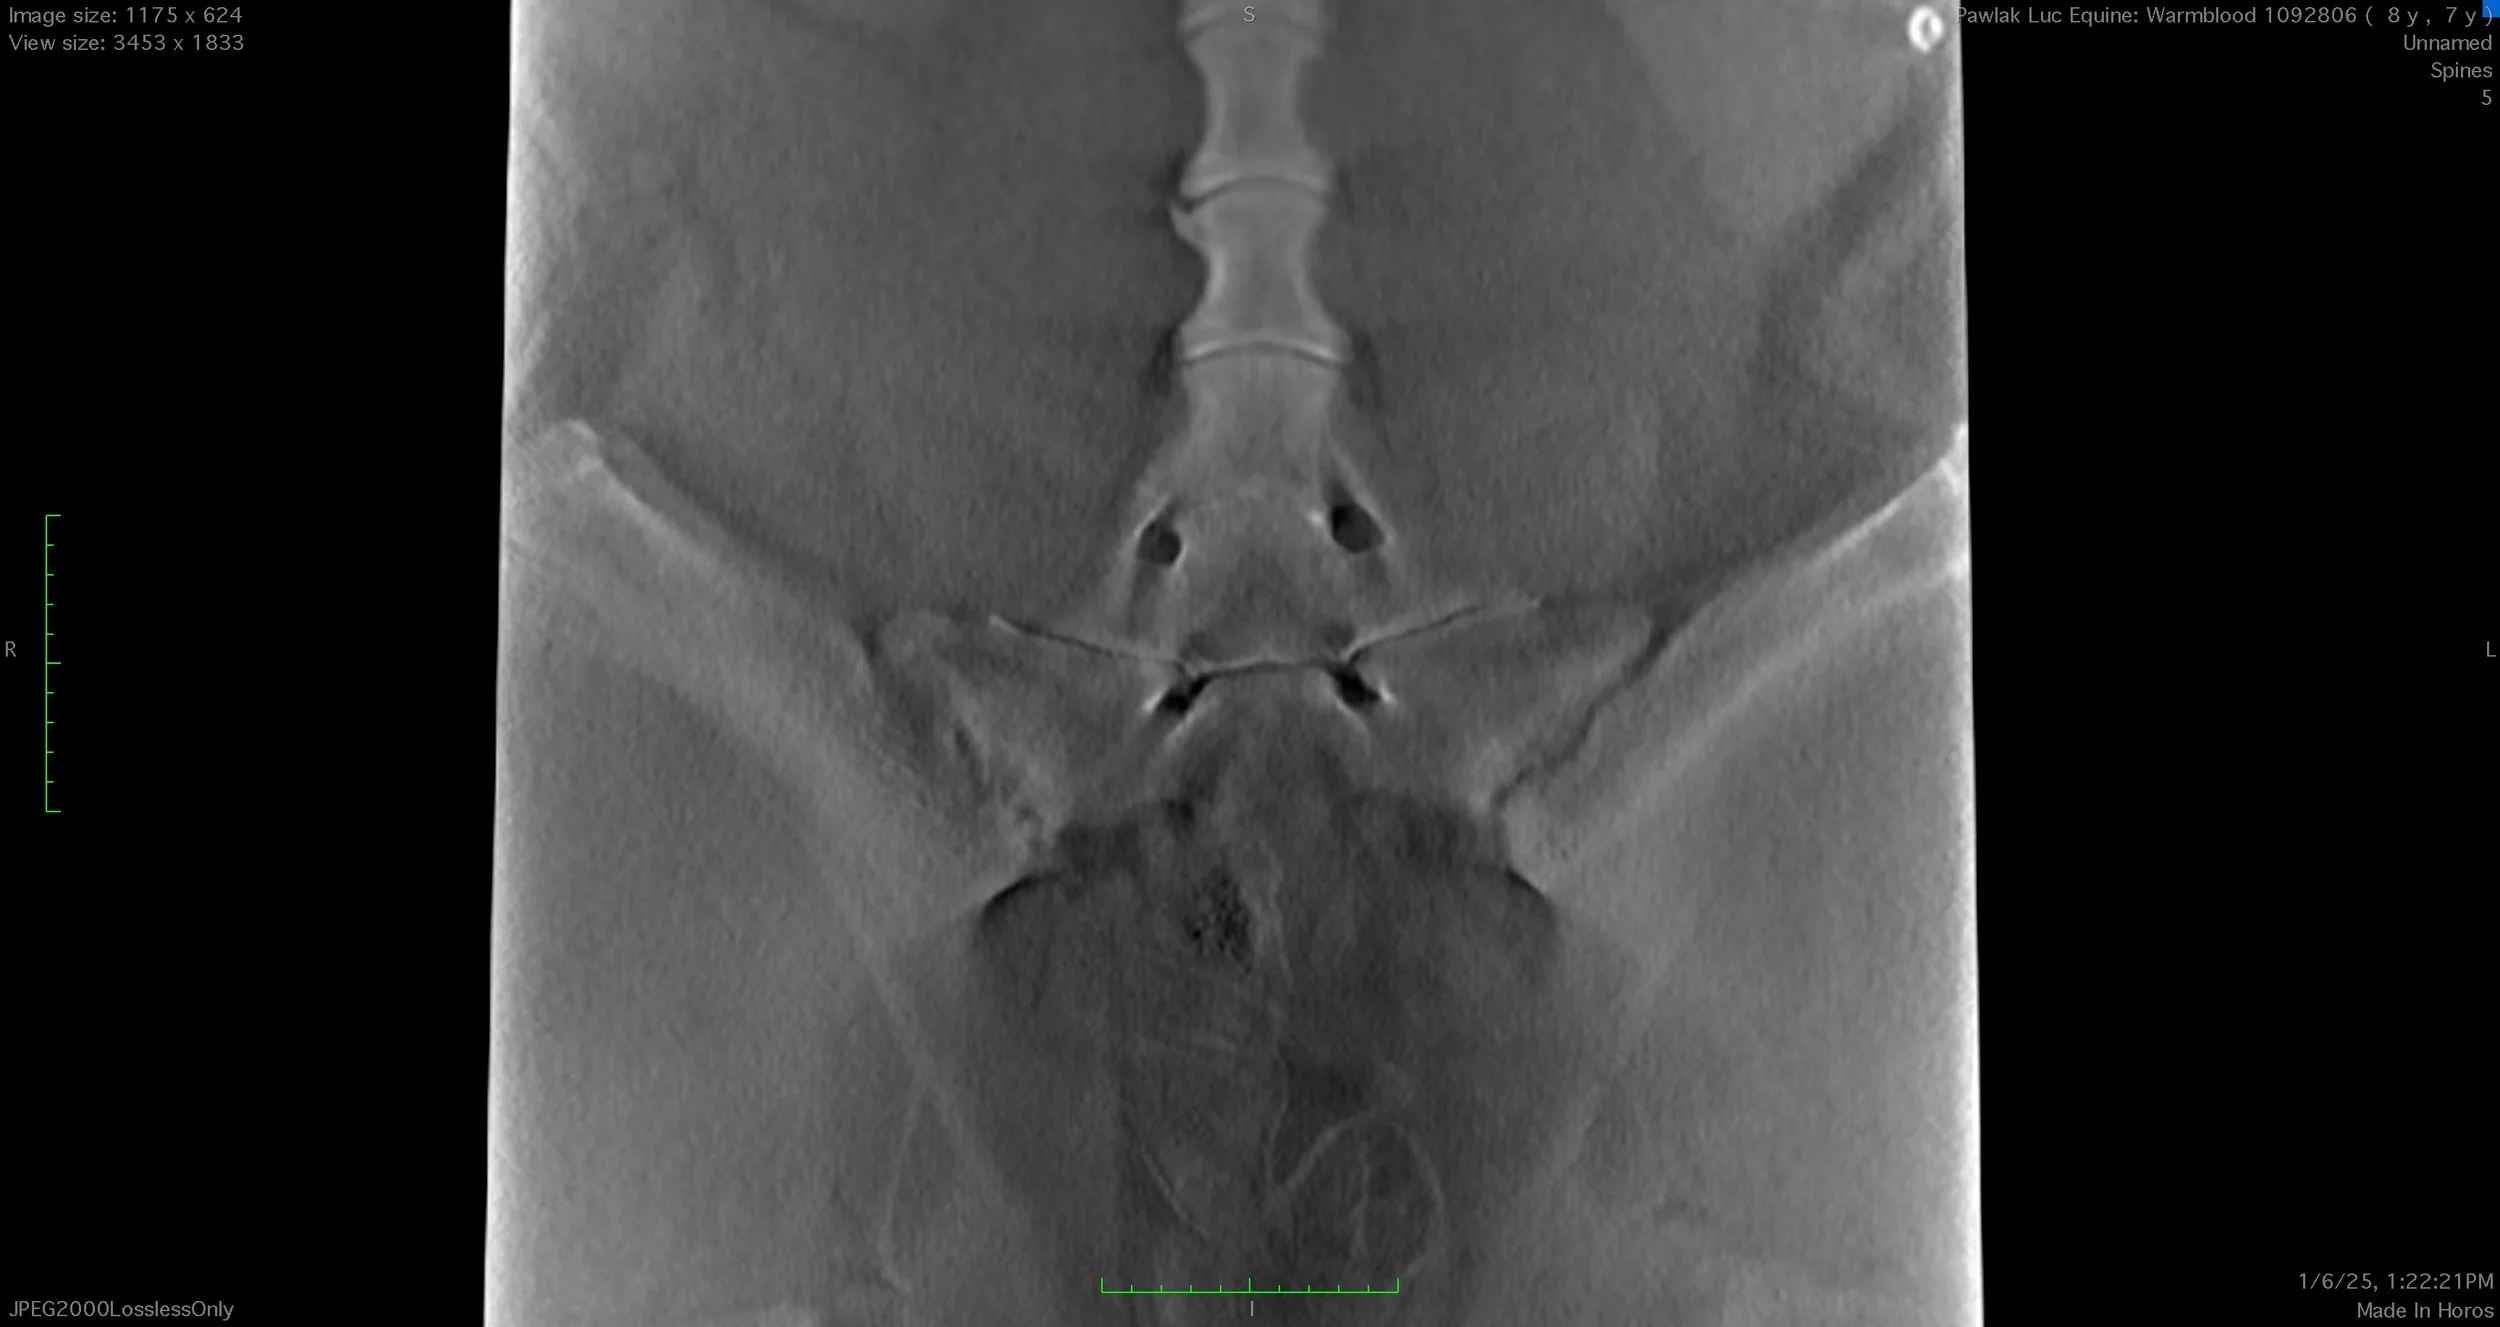

Professional reports with key images for all diagnostic imaging modalities, including radiographs, ultrasound, CT, MRI, nuclear scintigraphy.